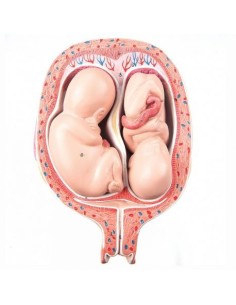

Dal cranio in 22 parti con incastri magnetici ai modelli di colonna vertebrale, da quelli di articolazioni a quelli di cuore, ogni pezzo della nostra collezione è progettato per un’immersione totale nello studio dell’anatomia umana. I nostri modelli, realizzati tramite scansioni di ossa vere, garantiscono un’esperienza tattile autentica e una fedeltà di peso quasi identica agli originali.

Essenziali per studenti e professionisti, i nostri modelli anatomici sono strumenti didattici che permettono di osservare le strutture anatomiche con precisione, eliminando la necessità di dissezioni o studi invasivi. Sono inoltre utili per spiegare ai pazienti le patologie, rendendo la comunicazione più efficace e risparmiando tempo prezioso.